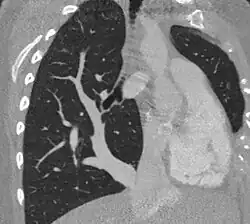

| Scimitar syndrome chest CT | |

Scimitar syndrome, or congenital pulmonary venolobar syndrome, is a rare congenital heart defect characterized by anomalous venous return from the right lung (to the systemic venous drainage, rather than directly to the left atrium).[1] This anomalous pulmonary venous return can be either partial (PAPVR) or total (TAPVR). The syndrome associated with PAPVR is more commonly known as Scimitar syndrome after the curvilinear pattern created on a chest radiograph by the pulmonary veins that drain to the inferior vena cava.[2] This radiographic density often has the shape of a scimitar, a type of curved sword.[2] The syndrome was first described by Catherine Neill in 1960.[3]

The diagnosis is made by transthoracic or transesophageal echocardiography and selective pulmonary angiography.[5] More recently by CT angiography or MR Angiography.

Pulmonary angiography demonstrates anomalous arterial supply to right lower lobe.[5]